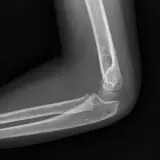

Over 2,100 interactive radiology cases, curated by radiologists for your level of training. Scroll, window, and view cases full screen โ€” just like on PACS. Click linked findings in each writeup to jump straight to them on the image. Cases include sample reports, a focused discussion section, original illustrations, and videos.

Casi completamente interattivi con gli strumenti che ti aspetti su un PACS: scroll, windowing, zoom, pan, misurazioni, ROI e modalitร  a schermo intero.

Annotazioni dettagliate evidenziano i reperti chiave direttamente sui casi. Clicca sui reperti collegati nella descrizione del caso per saltare alla loro esatta posizione sullo scan.